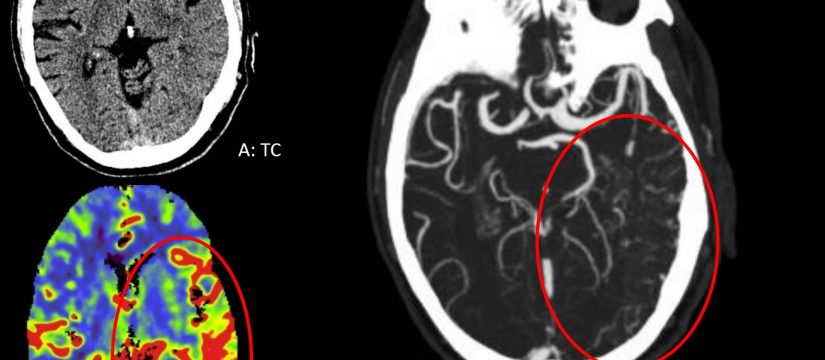

Mujer de 69 años de edad, con un cuadro de 7 meses de inestabilidad cefálica y de la marcha. Se realiza una RM craneal inicial, que es normal. Progresivamente, la síntomatología empeora, añadiéndose desorientación, alucinaciones, mioclonías y deterioro cognitivo. Se repite RM craneal por empeoramiento clínico progresivo.